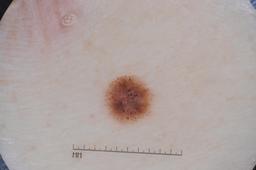

ISIC-DICM-17K (ISIC Dermoscopic Images and Clinical Metadata 17K) is a curated and balanced dataset derived from the International Skin Imaging Collaboration (ISIC) Archive Gallery. It comprises 17,060 dermoscopic images and clinical metadata (8,530 melanoma and 8,530 non-melanoma classes).

For more details, please follow the project’s GitHub repository: https://github.com/mmu-dermatology-research/isic-dicm-17k

This dataset was used in this study and benchmark to explore the effectiveness of multimodal learning for skin lesion classification:

S. Ahammed, X. Cui, W. Lu and M. H. Yap, "Skin Lesion Classification using Dermoscopic Images and Clinical Metadata: Insights from Multimodal Models," 2025 IEEE/CVF Conference on Computer Vision and Pattern Recognition Workshops (CVPRW), Nashville, TN, USA, 2025, pp. 222-230, DOI: 10.1109/CVPRW67362.2025.00027